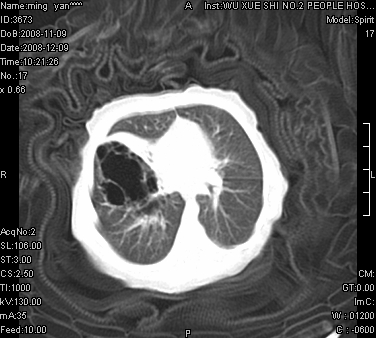

女.30天.咳嗽.喘3天.系三胞胎

考虑右肺下叶先天性肺囊肿,不除外合并右中叶肺发育不全

伴双肺感染

考虑右肺下叶先天性多发性肺囊肿可能。

考虑右肺下叶肺囊肿伴感染,右中叶节段实变或发育不全

这是一个先天性囊性腺瘤样畸形(congenital cystic adenomatid malformation,ccam),属于先天性肺发育异常,最近国外文献重新命名为先天性肺气道畸形(congenital pulmonary airway malformation,cpam),根据发生部位和畸形组织与气管、支气管的关系分成五型。本病以1岁以下婴儿多见,男性多于女性。病因为终末呼吸单元的异常增殖,形成多囊状结构。国内根据影响和病理表现分三型:ⅰ型为单个或多个大囊肿,直径大于2cm;ⅱ型为多个小囊肿,直径小于2cm;ⅲ型为大的非囊肿性病变,但显微镜下观察可见肿块由多发小囊组成(直径小于2mm)。本病可发生于肺内任何一部分,单侧肺占95%,中叶病变相对较少。